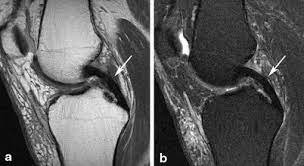

The knee joint relies on several ligaments for stability and function, including the medial collateral ligament (MCL), lateral collateral ligament (LCL), and posterior cruciate ligament (PCL). Injuries to these ligaments can result in pain, swelling, instability, and difficulty with knee movement. Complex ligament injuries, which involve damage to two or more ligaments, can significantly impact knee function and may require specialised treatment to restore stability and mobility.

• MCL (Medial Collateral Ligament): The MCL is located on the inner side of the knee and provides stability against forces that push the knee inward. MCL injuries are often caused by direct blows to the outside of the knee.

• LCL (Lateral Collateral Ligament): The LCL is located on the outer side of the knee and provides stability against forces that push the knee outward. LCL injuries are less common and often occur due to direct trauma or hyperextension.

• PCL (Posterior Cruciate Ligament): The PCL is located at the back of the knee and prevents the shinbone from moving backward relative to the thighbone. PCL injuries are often caused by high-impact trauma, such as car accidents or falls.

• Complex Ligament Injuries: These involve damage to two or more ligaments, often resulting from high-energy trauma such as sports injuries or motor vehicle accidents. Complex injuries may also affect other knee structures, such as cartilage or menisci.